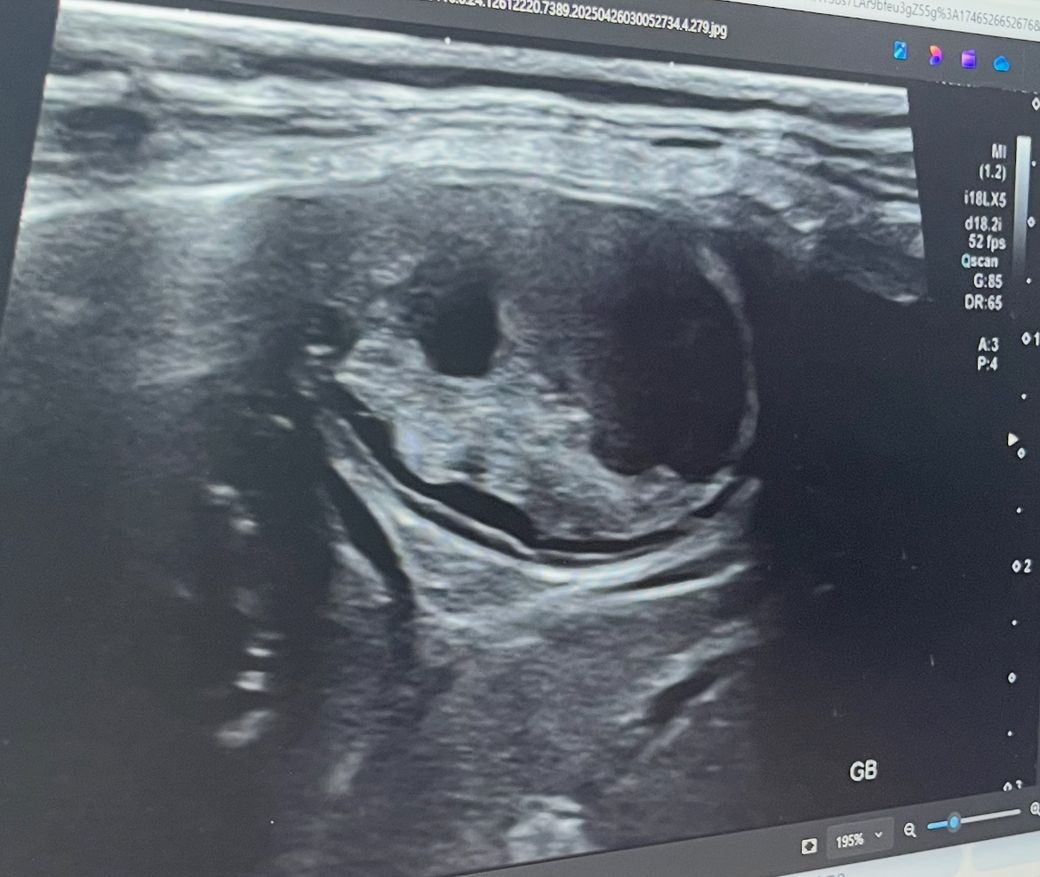

안녕하세요. 15살 시츄를 키우고 있습니다 최근 간 수치가 좋지 않아 큰 병원에 입원해 4일간 집중 치료를 받았고, 다행히 수치는 많이 안정된 상태입니다 입원 당일 촬영한 사진입니다

담낭점액종이 위험한 질환이라고 들었는데, 촬영한 영상 상으로 당장 수술이 필요한 상태인지 궁금합니다 의료진 설명에 따르면 담관이 막힌 상태는 아니라고 들었습니다

점액종 가능성이 높아 보이지만 positional study를 해봐야 진단적 가치를 높일 수 있습니다.

또한 점액종의 경우 그 단계의 정도와 담낭의 파열간의 통계적 유의성이 없는게 정설입니다.

즉, 점액종 초기나, 점낵종 말기나 담낭이 터지는 비율은 동일하다는게 정설이니, 점액종으로 확인되는 경우 내과 혹은 외과적 개입이 일차적으로 추천됩니다.